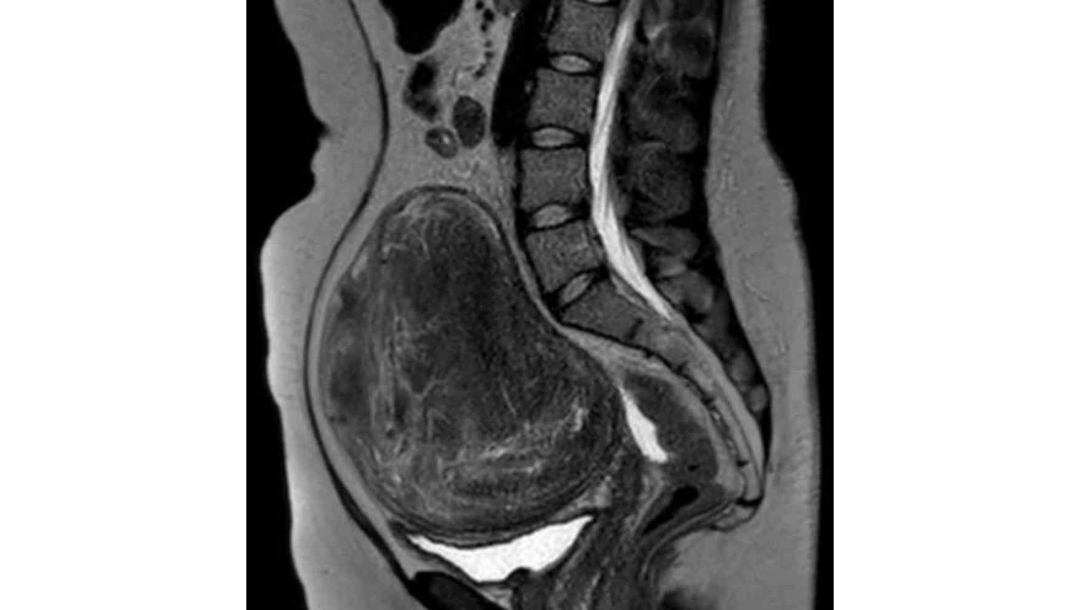

Kimber had successful surgery to remove an extremely large uterine fibroid on July 25th.

“I've had symptoms for roughly ten years with physically obvious (could see a bump in my abdomen) symptoms for two years.

I saw around six different doctors in three states before I was taken seriously and by then it was big and growing rapidly.

All of the tumors were fused together into one massive piece that weighed twenty times a normal uterus and spread front to back and around the side.“